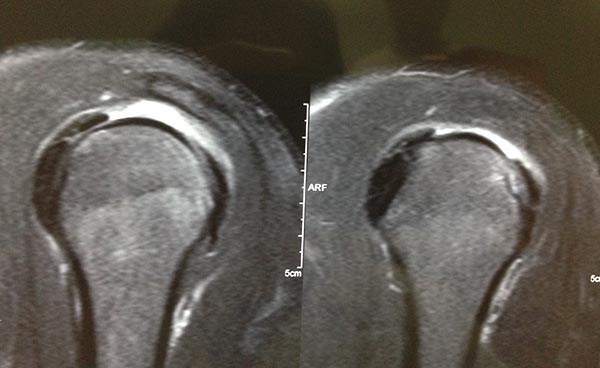

Tear size was defined via preoperative magnetic resonance imaging (MRI) and/or during surgery with a measuring probe; when both were available, surgical measurements took precedence over MRI data (figs. 1, 2, and 3). Tears were classified according to Cofield et al. as small (<1 cm), medium (1–3 cm), large (3–5 cm), or massive (>5 cm).1, 9

Figure 1: Magnetic resonance image (sagittal view) showing a tear in the supraspinatus tendon.

Figure 2: Magnetic resonance image (coronal view) showing a tear in the supraspinatus tendon.